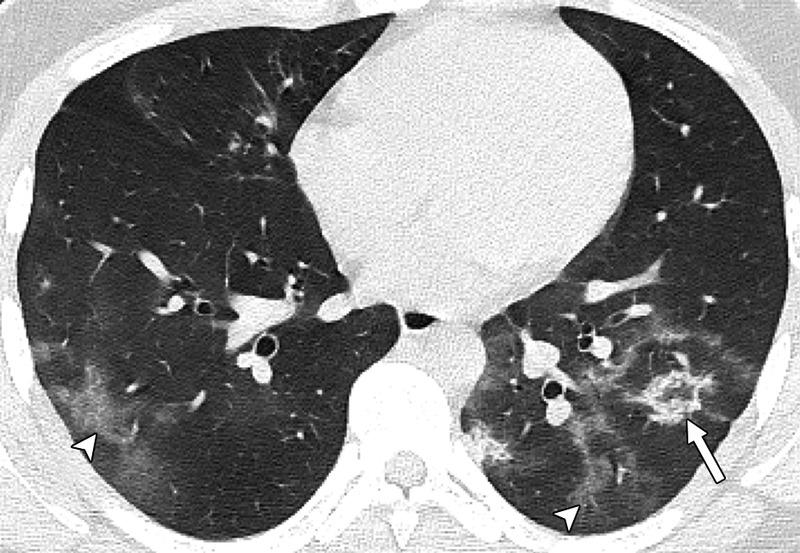

Μία εικόνα χίλιες λέξεις. Αξονικές τομογραφίες νέων κάτω από 18 έτη με Covid-19 (18 ετών, 15 ετών, 14 ετών και 8 ετών). Κανένας ασθενής δεν είχε υποκείμενα νοσήματα ή ανοσοκαταστολή. Οι ασθενείς δεν χρειάστηκαν συμπληρωματικό οξυγόνο, διασωλήνωση ή ΜΕΘ. Πρόκειται για απλά-κοινά περιστατικά Covid-19.

Ωστόσο έχουν πολύ “εντυπωσιακές” βλάβες και είναι άγνωστο τι θα προκαλέσουν αυτές οι βλάβες σε βάθος χρόνου. Για την πλειονότητα του κόσμου το ερώτημα είναι απλό: Θέλουν να υποβάλουν τους πνεύμονές τους σε αυτές τις βλάβες για να δουν αν αντέχουν; Και αν αντέξουν την πρόκληση (όπως προβλέπεται ότι θα αντέξουν οι περισσότεροι νέοι) θέλουν να δουν πόσα χρόνια ή αντοχές έχασαν στην πορεία; Με το εμβόλιο προστατεύουμε τους πνεύμονές μας από βαρύτατη καταπόνηση!